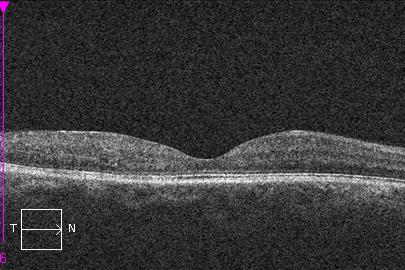

La realización de una tomografía de coherencia óptica (OCT) permite objetivar el grado de edema macular diabético y valorar la evolución y respuesta al tratamiento.

OCT. Edema macular diabético antes del tratamiento con inyecciones intravítreas.

OCT. Edema macular diabético después del tratamiento con inyecciones intravítreas.